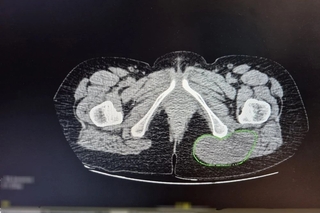

Результат оказался пугающим: после активного механического воздействия опухоль начала стремительно увеличиваться и достигла 10 сантиметров. Обследование в БГКБ (УЗИ, компьютерная томография и биопсия) показало, что «жировик» оказался злокачественным новообразованием, выросшим из жировой ткани.